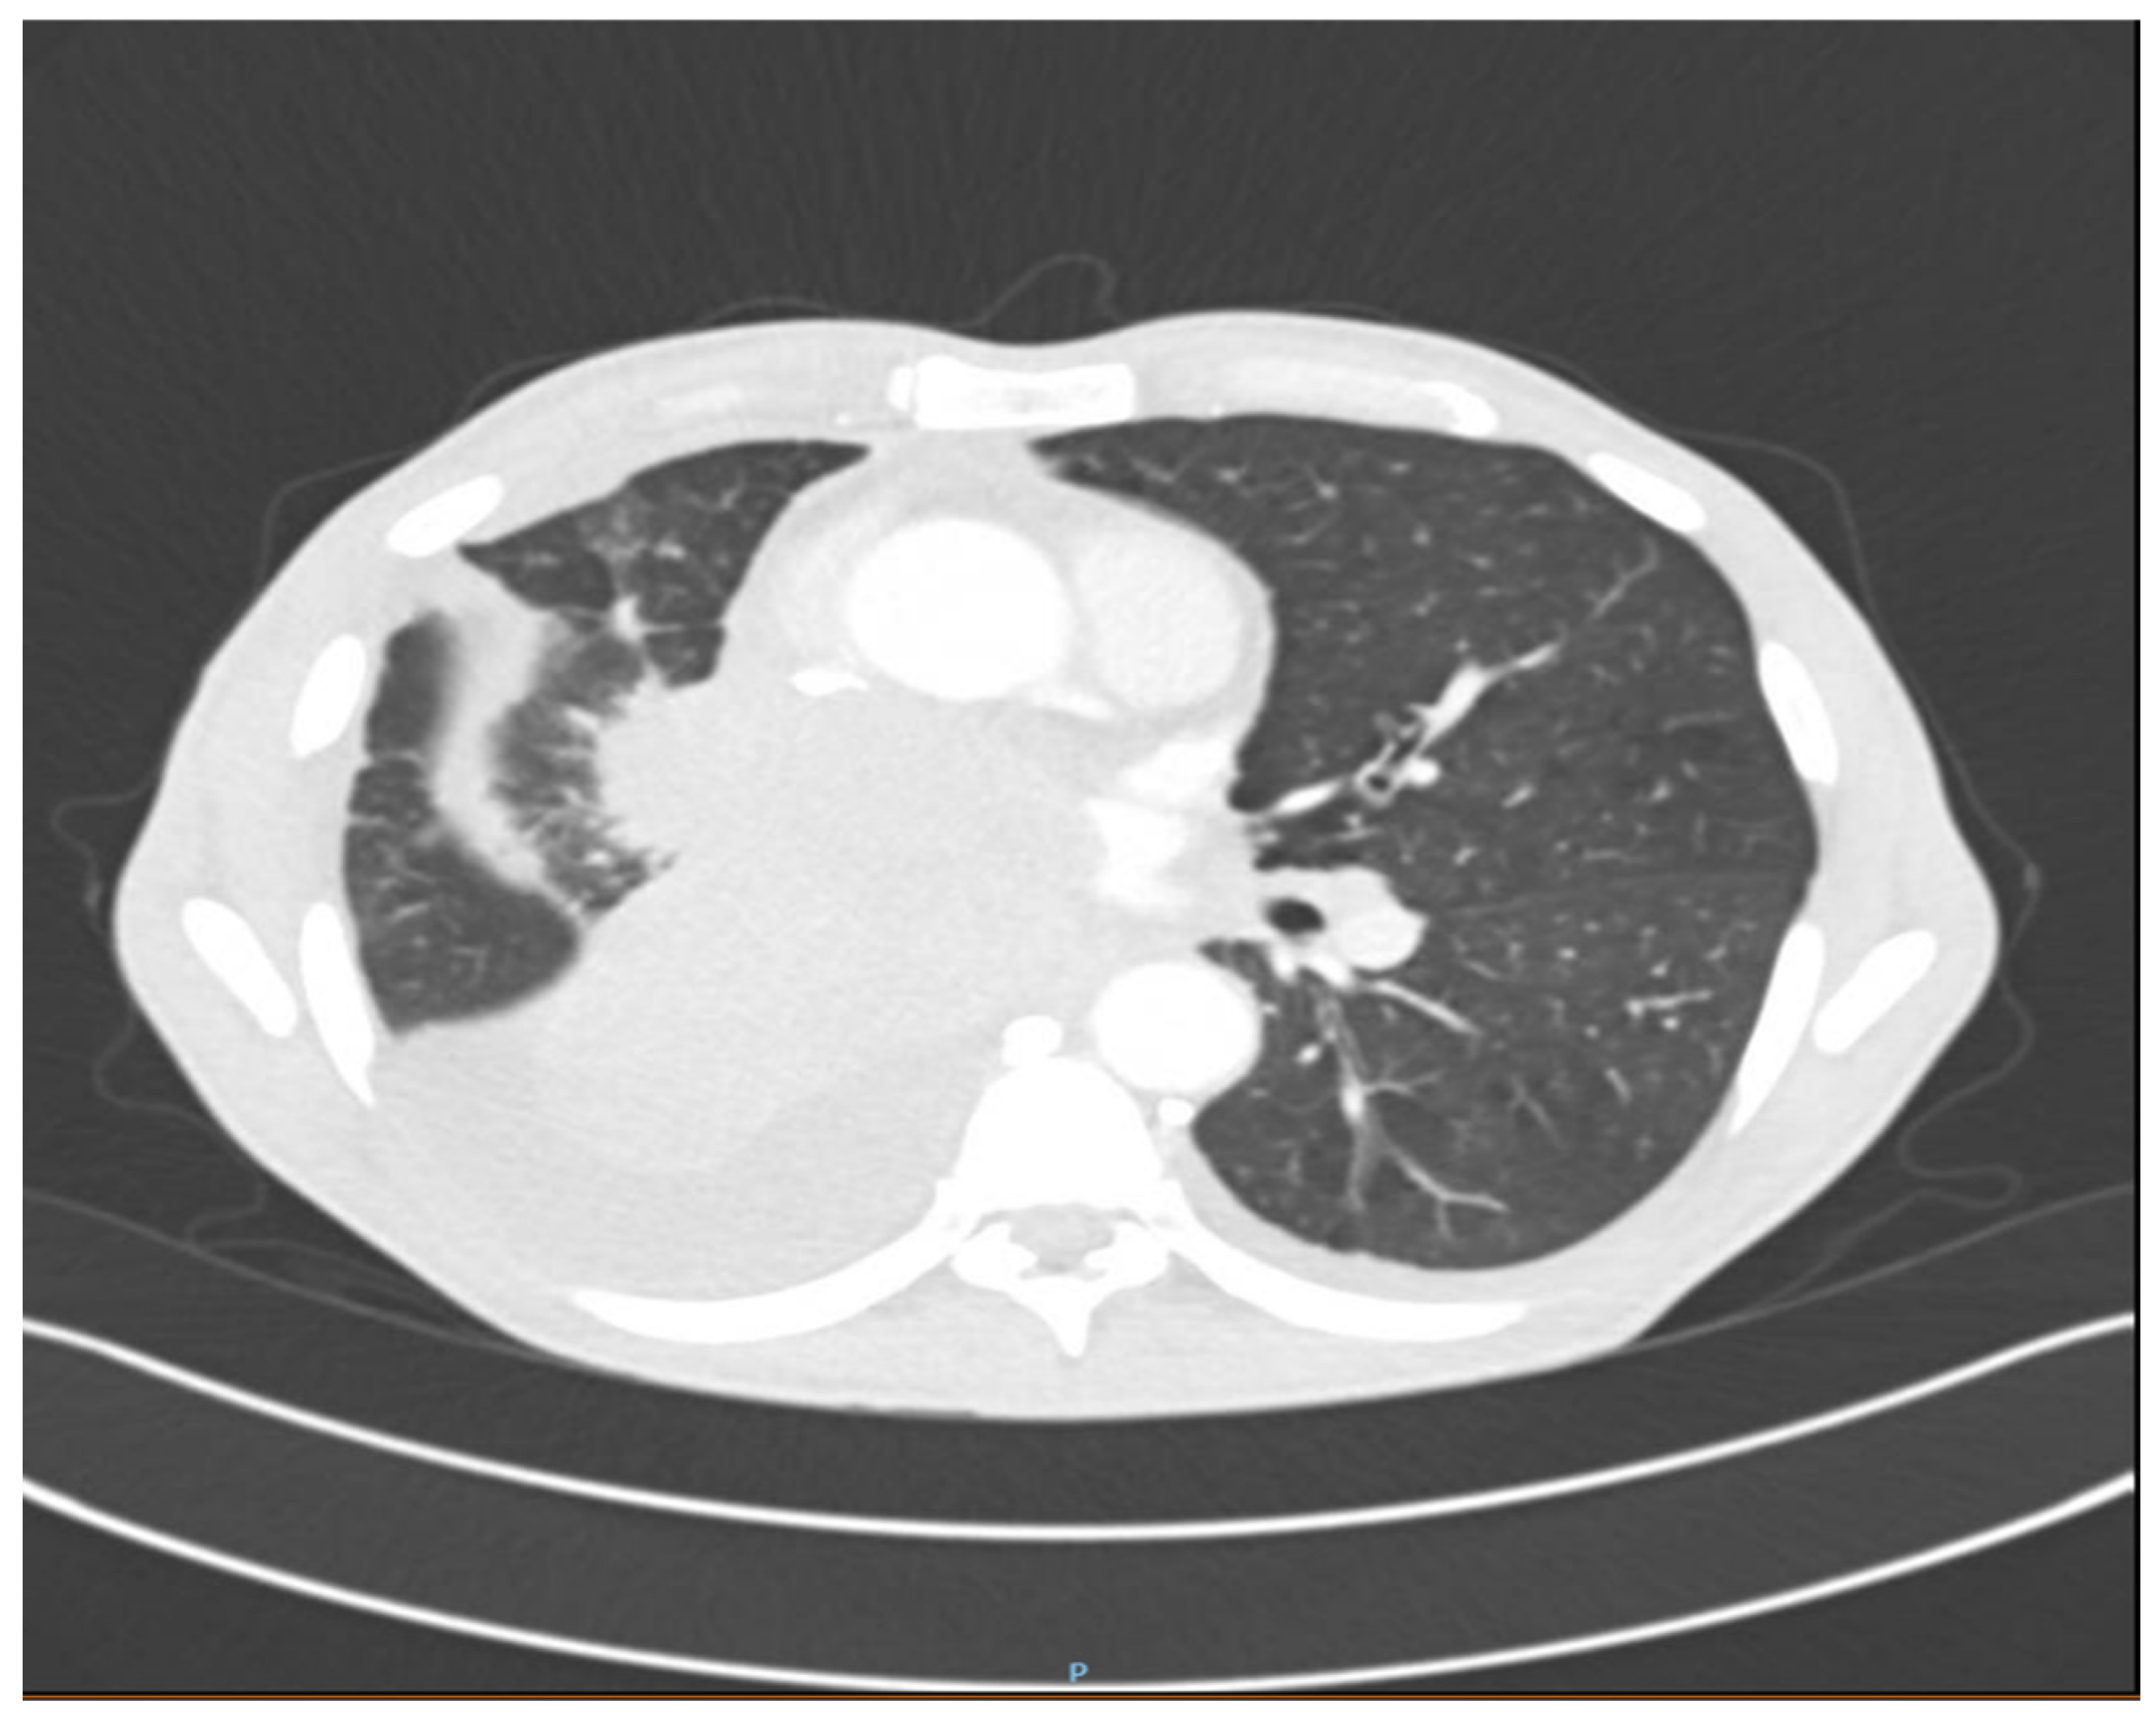

2. Detailed Case Description

2.1. Diagnostic Evaluation